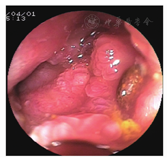

血常规检查显示,RBC计数为3.51×1012/L(下降),平均Hb量为19.4 pg(下降),平均Hb浓度为288 g/L(下降),PLT计数为489×109/L(升高)。尿常规检查阴性。肝肾功能:葡萄糖为8.81 mmol/L(升高),前白蛋白为97 mg/L(下降),白蛋白为32 g/L(下降),肌酐为43 μmol/L(下降),钾离子为3.30 mmol/L(下降)。癌抗原72-4为88.96 kU/L(升高),AFP、CEA、CA125、CA19-9、癌抗原242、癌抗原15-3均阴性。小肠CT检查(图1)显示,左上腹空肠肠壁增厚,最厚处约3 cm,形成软组织肿块伴溃疡形成,病灶密度不均匀,平扫CT平均值为42 Hu,增强后动脉期平均值为65 Hu,门静脉期平均值为75 Hu,局部肠腔扩张,周围肠管结构欠清,周围系膜密度增高,多枚淋巴结影显示部分肿大(最大径>1 cm),呈轻度强化,可见病灶中肠系膜血管呈夹心面包征;直肠壁稍厚。小肠CT检查诊断意见为左上腹空肠占位性病变,首先考虑淋巴瘤,不典型腺癌待排。小肠镜检查(图2)显示至十二指肠中段,乳头下方10 cm处见黏膜隆起增生,触之易出血,肠腔狭窄,小肠镜无法通过,取4块组织行活组织检查。小肠镜检查诊断意见为十二指肠中段隆起增生。

术前的小肠CT表现更偏向于淋巴瘤的诊断,而小肠镜检查因十二指肠的梗阻,未完成对病变小肠的标本取样,失去了最有力的诊断依据。术后也证实十二指肠受侵犯造成狭窄。